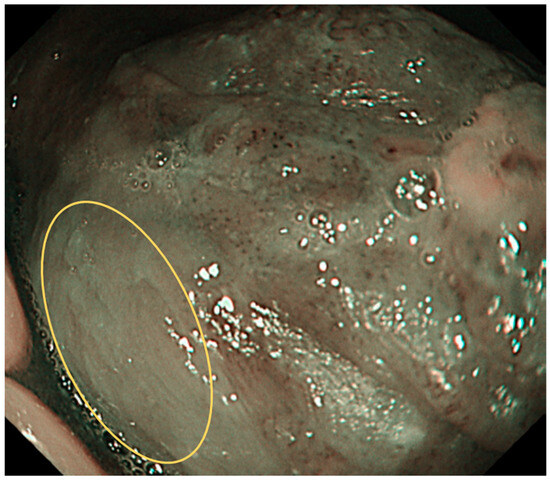

6. NBI Magnification Endoscopy of Oral Lesions

7. Interpretation of IPCLs